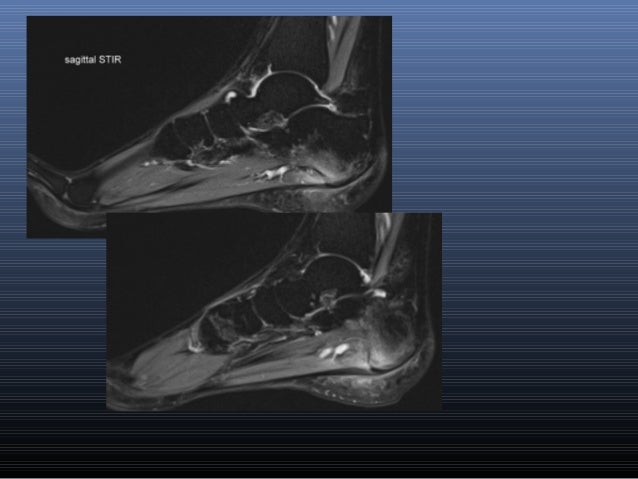

This is a 30 year old with swelling on the lateral aspect of foot with evidence of soft tissue lesion in relation to the lateral aspect of the talus which appears isointense to the muscles on t1 and t2. Indications for foot mri scan. Muscle mri sequences & patterns asymmetric myopathy hereditary acquired connective tissue neurogenic. Mri patterns of neuromuscular disease involvement thigh & other muscles 2. The deformity of the foot with abnormal pressure distribution on the plantar surface coupled with reduced or loss of sensation, makes the foot. Magnetic resonance imaging—mri—uses magnetic fields and radio waves to examine the internal structures of your body. Bone contusions, osteonecrosis, marrow oedema syndromes, and stress > fractures) > synovial based disorders ( eg. Learn about foot and ankle mri here.